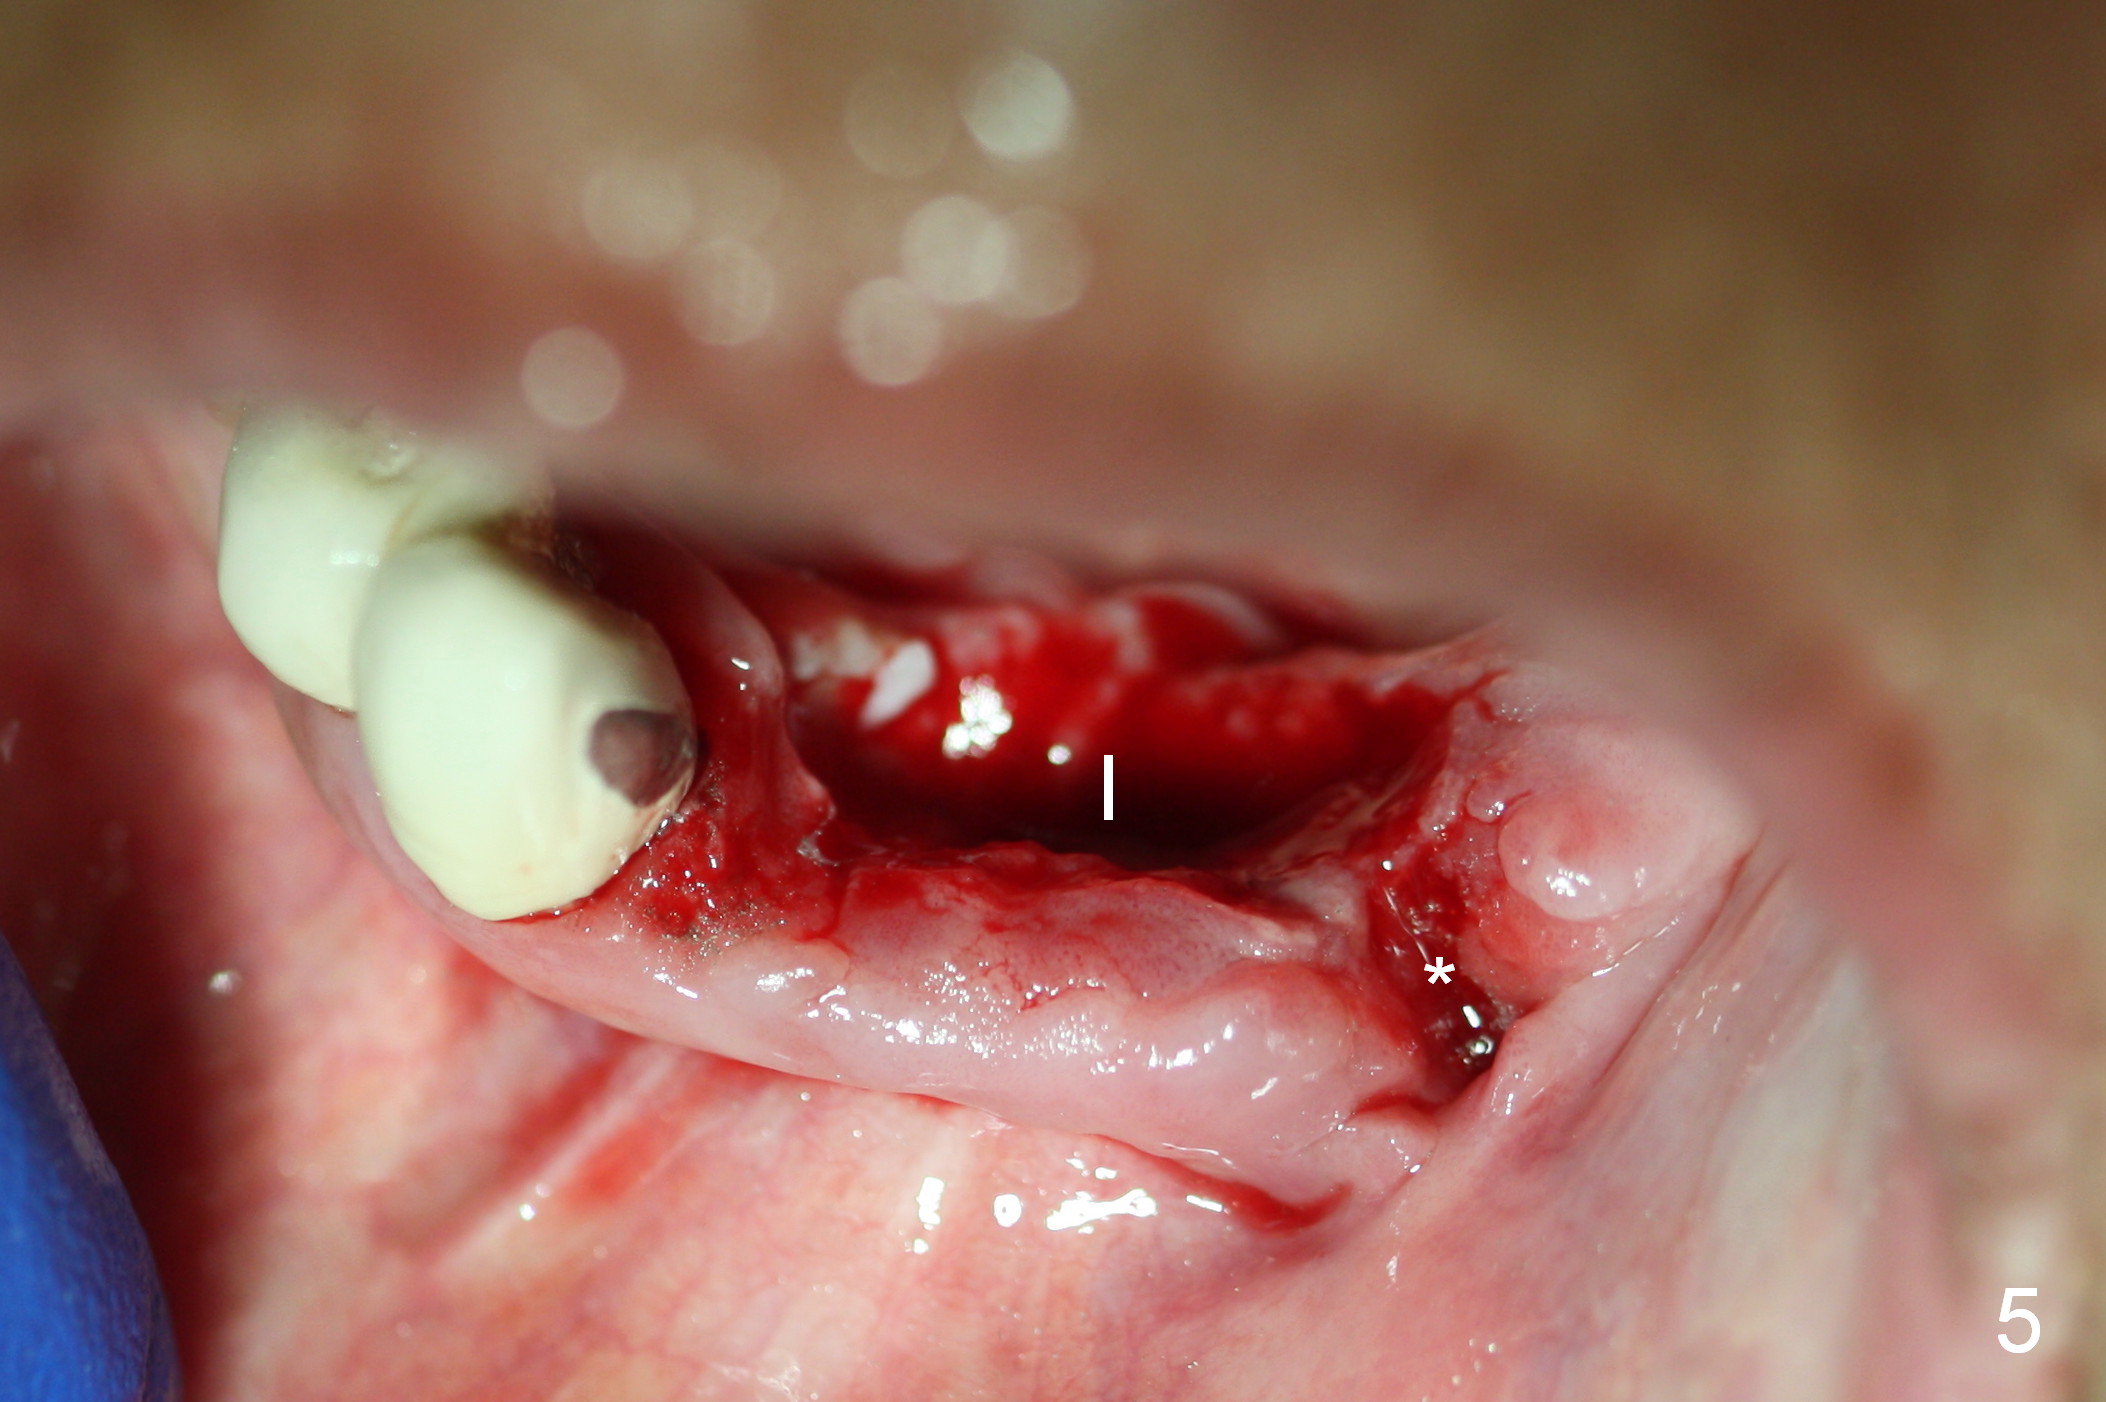

A 72-year-old woman has severe pain associated with one of three abutments of a long-spanned bridge (Fig.1,2: #22). The lingual calculus is extremely large (Fig.3 C). When the bridge is sectioned between #26 and 27, the tooth #22 is easily separated from the socket (Fig.4). In fact, the large supragingival calculus causes hemorrhagic indentation in the lingual vestibule (Fig.5,6: I). Due to finance, socket preservation is done at #22 with 6-month collagen membrane buccally and .5-1.5 mm allograft and collagen plug (Fig.6 *).